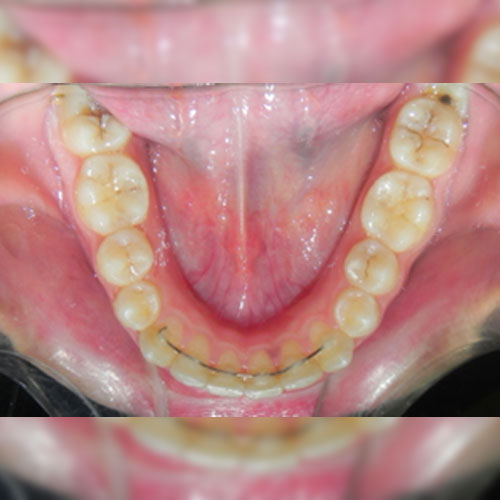

Smile Transformations

Real Patient Smile Transformations